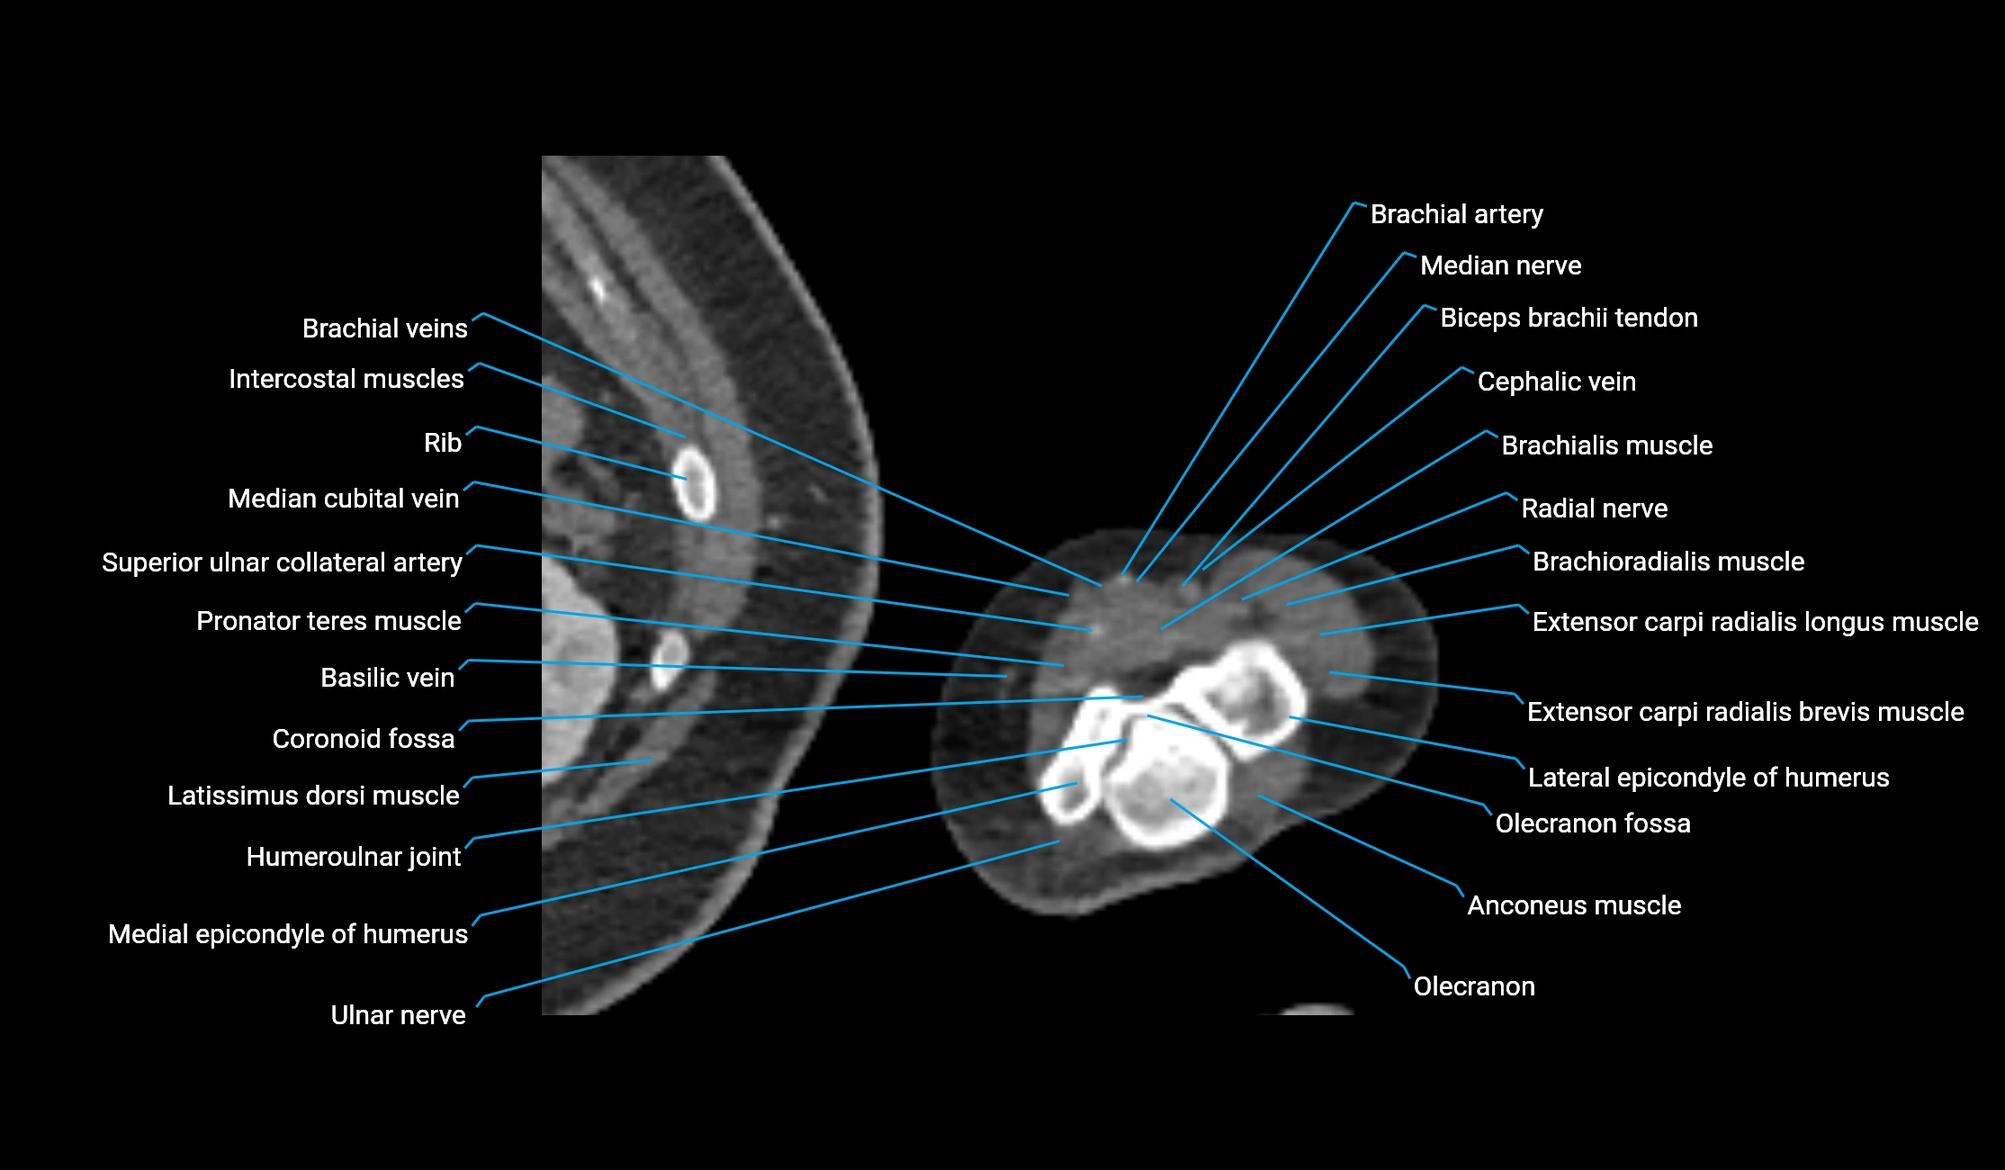

- Humeroulnar joint

- Humeroradial joint

- Coronoid fossa

- Olecranon fossa

- Olecranon

- Lateral epicondyle of humerus

- Medial epicondyle of humerus

- Medial supracondylar ridge

- Median cubital vein

- Brachial artery

- Median nerve

- Pronator teres muscle

- Extensor carpi radialis brevis muscle

- Extensor carpi radialis longus muscle

- Brachioradialis muscle

- Radial nerve

- Cephalic vein

- Biceps brachii tendon (distal)

- Anconeus muscle

- Basilic vein

- Ulnar nerve

- Superior ulnar collateral artery

- Inferior ulnar collateral artery